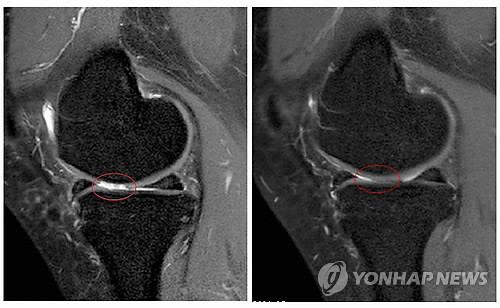

- ▲ 아래 기사내용과는 무관함

운동선수나 노년층이 주로 하는 무릎 관절 수술이 의학적으로 아무런 효과가 없다는 연구결과가 발표돼 화제다.최근 의학전문지 '뉴잉글랜드 저널 오브 메디신'에 실린 핀란드 헬싱키 대학 연구팀의 연구 결과에 따르면 무릎 부상으로 연골 수술을 받은 사람과 받지 않은 사람 사이에 큰 차이가 없는 것으로 전해졌다.헬싱키대학 연구팀은 운동이나 노화로 무릎 연골에 이상이 생긴 환자 146명을 두 그룹으로 나눠 1년 뒤 부상 회복 정도를 비교했다.그 결과 실제 수술을 받은 환자와 수술을 받지 않은 환자 사이에 완쾌 정도는 비슷하게 나타났다.연구팀은 "이번 결과는 노화로 인한 퇴행성 무릎 연골 부상에 습관적으로 수술하는 것이 논란의 소지가 있음을 보여줬다"고 강조했다.하지만 이번 열구 결과를 놓고 미국 내 전문가들의 의견도 크게 엇갈리고 있는 상황이다.메릴랜드 의대 크레이그 베넷 스포츠의학 교수는 "이번 결과를 일반화 할 수 없다"며 "연골 조각이 떨어져 나가 무릎이 부은 환자에게 수술은 효과가 있다"고 비판했다.또 보스턴 브리검 앤드 여성병원의 제프리 카츠 교수는 "무릎 연골 수술을 받으면 약간의 도움은 되지만 수술 효과가 오래 가지는 못한다"고 주장했다.한편, 무릎 관절 수술 효과 소식을 접한 네티즌들은 "그래서 하란거야 말란거야" "효과가 없다고?" "의사들 다 사기꾼 같아" "효과 없으면 한사람 억울하겠다" 등의 반응을 보였다.[사진 출처=연합뉴스]